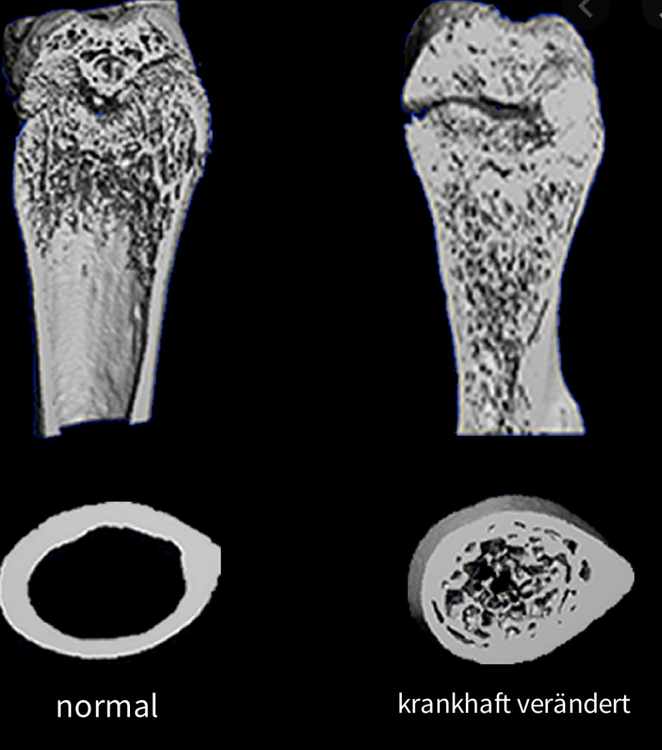

Osteopetrose?

!Verminderte! Osteoklastenaktivität